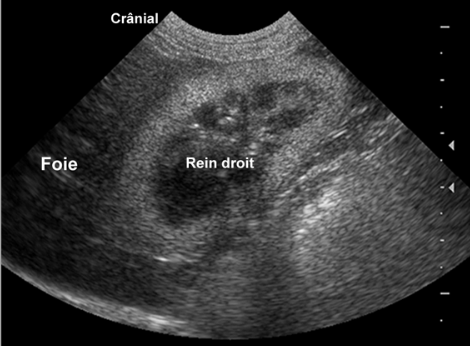

Que remarquez-vous d’anormal?

rein hyperéchogène par rapport au foie : anormal !

ici : intoxication éthylène glycol